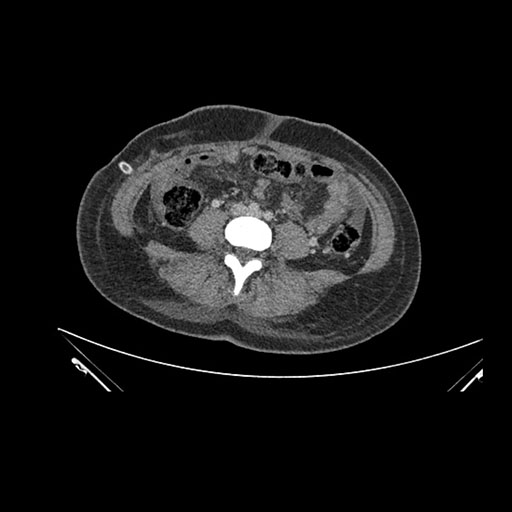

Imaging Analysis

Look through the patient's CT scan to identify any areas of concern for the necessary procedure.

Axial Arterial